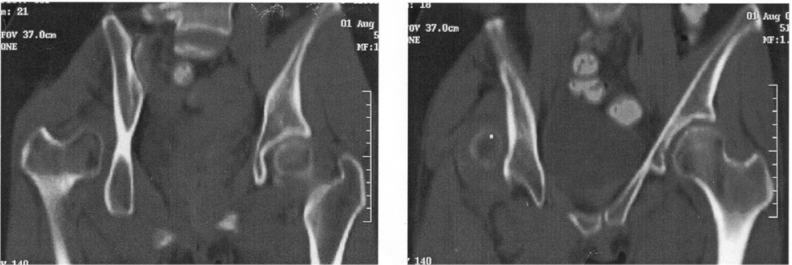

17 一位 40 歲男性病患,主要症狀為右側臉部腫脹疼痛感並合併有右眼複視,除此之外並無合併其他症 狀,病患 15 年前有接受過上頜竇手術的病史;其鼻竇電腦斷層顯示如下圖所示;其較可能的診斷為 何?

(A)急性鼻竇炎 (B)黏液囊腫 (C)鼻竇腫瘤 (D)橫紋肌瘤